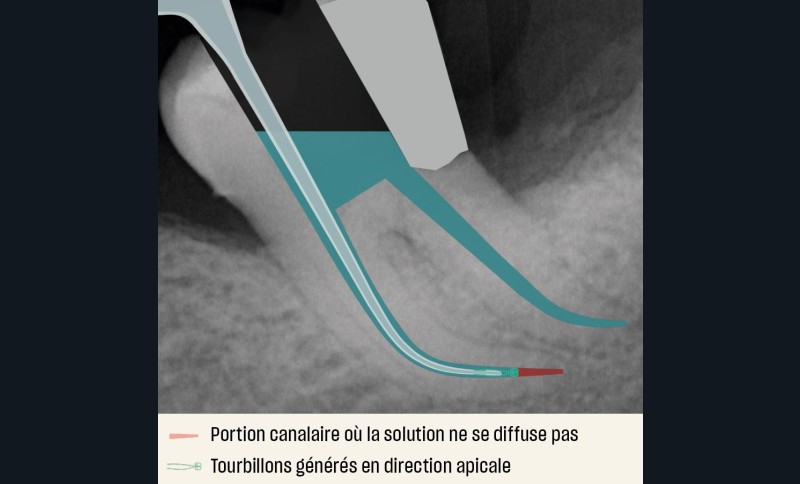

Dans les préparations canalaires conservatrices, de nouvelles technologies telles que l’Irriflex® et le laser Erbium YAG sont intéressantes pour optimiser la désinfection et l’élimination des tissus organiques pulpaires et non organiques dentinaires [25, 26]. L’Irriflex® est une canule d’irrigation en polypropylène, donc souple, qui a su se distinguer par sa conicité à 4 %. Son calibrage adapté au canal et sa double sortie latérale assurent un renouvellement continu de la solution d’irrigation à l’extrémité de la canule. La diffusion de la solution entraîne des tourbillons, de l’extrémité de l’aiguille vers la partie coronaire, augmentant ainsi les phénomènes hydrodynamiques. Cependant le phénomène de diffusion reste limité à 1 mm au-delà de la pointe de l’aiguille [27] (fig. 12).